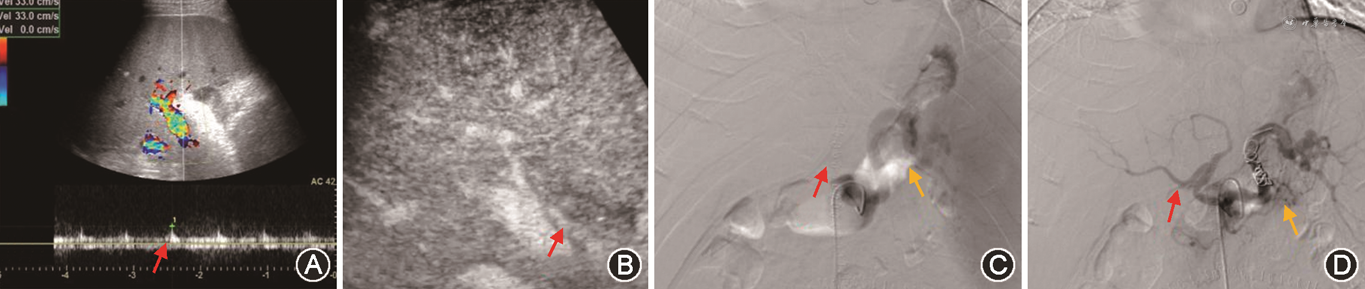

(4)脾动脉窃血综合征(splenic artery steal syndrome,SASS):SASS是指扩张的脾动脉从肝动脉处窃取或抢夺了血流,使得肝动脉向肝实质内血流灌注减少的一种现象。SASS发生率为3.1%~5.9%,主要发生在具有脾功能亢进、脾动脉相对增宽的肝硬化患者。SASS多发生在移植术后2个月内,是急性HAT重要原因之一。SASS发生时,CDFI在肝内、外动脉测及低速高阻血流(PSV<35 cm/s,RI>0.8),同时可见脾肿大、脾动脉增宽[66]。超声造影表现为肝动脉延迟出现(肝动脉与门静脉造影剂出现的时间差缩短)、显影暗淡;同时可见门静脉显影明显增强[67, 68](图15)。需注意,超声造影发现肝动脉延迟出现且显影暗淡时,还需排除其他导致移植肝动脉低灌注的原因如肝动脉血管收缩、HAS等,联合应用超声造影及CDFI检查可进行鉴别,流程如图16所示[33,69]。